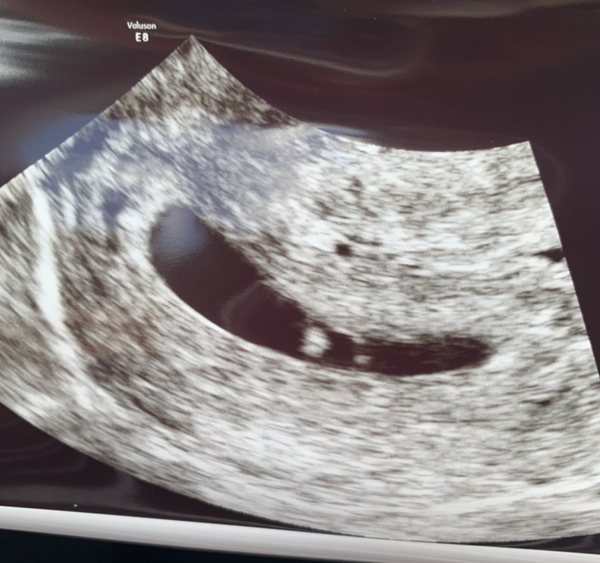

Kona84 · 04/10/2021 18:51

This is my HR for my pregnancy I got my positive early feb. It fluctuates frequently

Thanks for your chart, mines only just slightly higher than prepregnancy so nice to see it will probably rise still :) sorry to hear you’ve had GD, hope you’ve got under control.